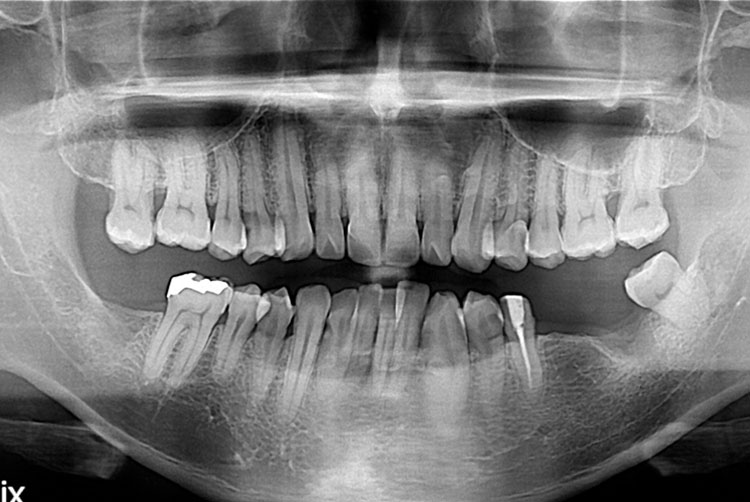

[임플란트] 임플란트

치료후 : 2017-07-20

세종치과는 많은 환자와 다양한 케이스를 바탕으로 항상 편안한 임플란트 수술을 제공하고자 노력하고,

오래동안 튼튼히 쓸 수 있는 임플란트 수술을 가장 큰 목표로 삼고 있습니다.